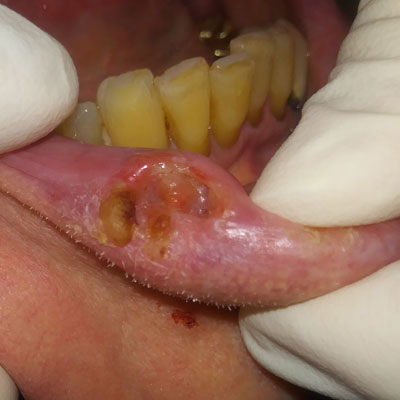

What conditions can cause ulcers in the mouth?

• Recurrent mouth ulcers -also known as canker sores -are one of the primary cause of mouth soreness that could result in significant discomfort to the patient.

Although most of the ulcers are painful, in certain situations such as certain mouth cancers, these could be painless. These include ulcers associated with Squamous Cell Carcinoma, Lymphoma, Melanoma, Sarcoma, etc.